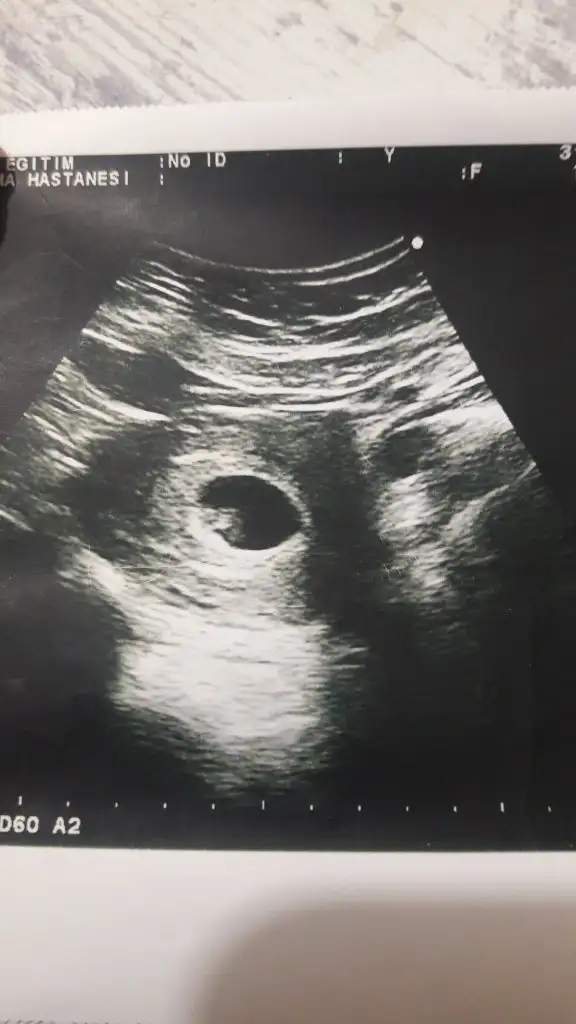

Bunlar da benim ultrason görüntülerim. İlki 6+5. İkincisi 8+1. İkisi de karından ultrason. Cinsiyet tahmini yapabilir misiniz?Yaaa rabbim bu defa saglıkla nasip etsin inşallah. şimdi kaç haftalık hamilesiniz dünkü 7 + olan sizin 6+4 olan arkadaşınızmı o zaman şimdilik ikiside kız görünüyor siz 11 yada 12 hafta paylaşın

Yolk saç solda erkek 6.5 usg de 8+1 de soldaBunlar da benim ultrason görüntülerim. İlki 6+5. İkincisi 8+1. İkisi de karından ultrason. Cinsiyet tahmini yapabilir misiniz?